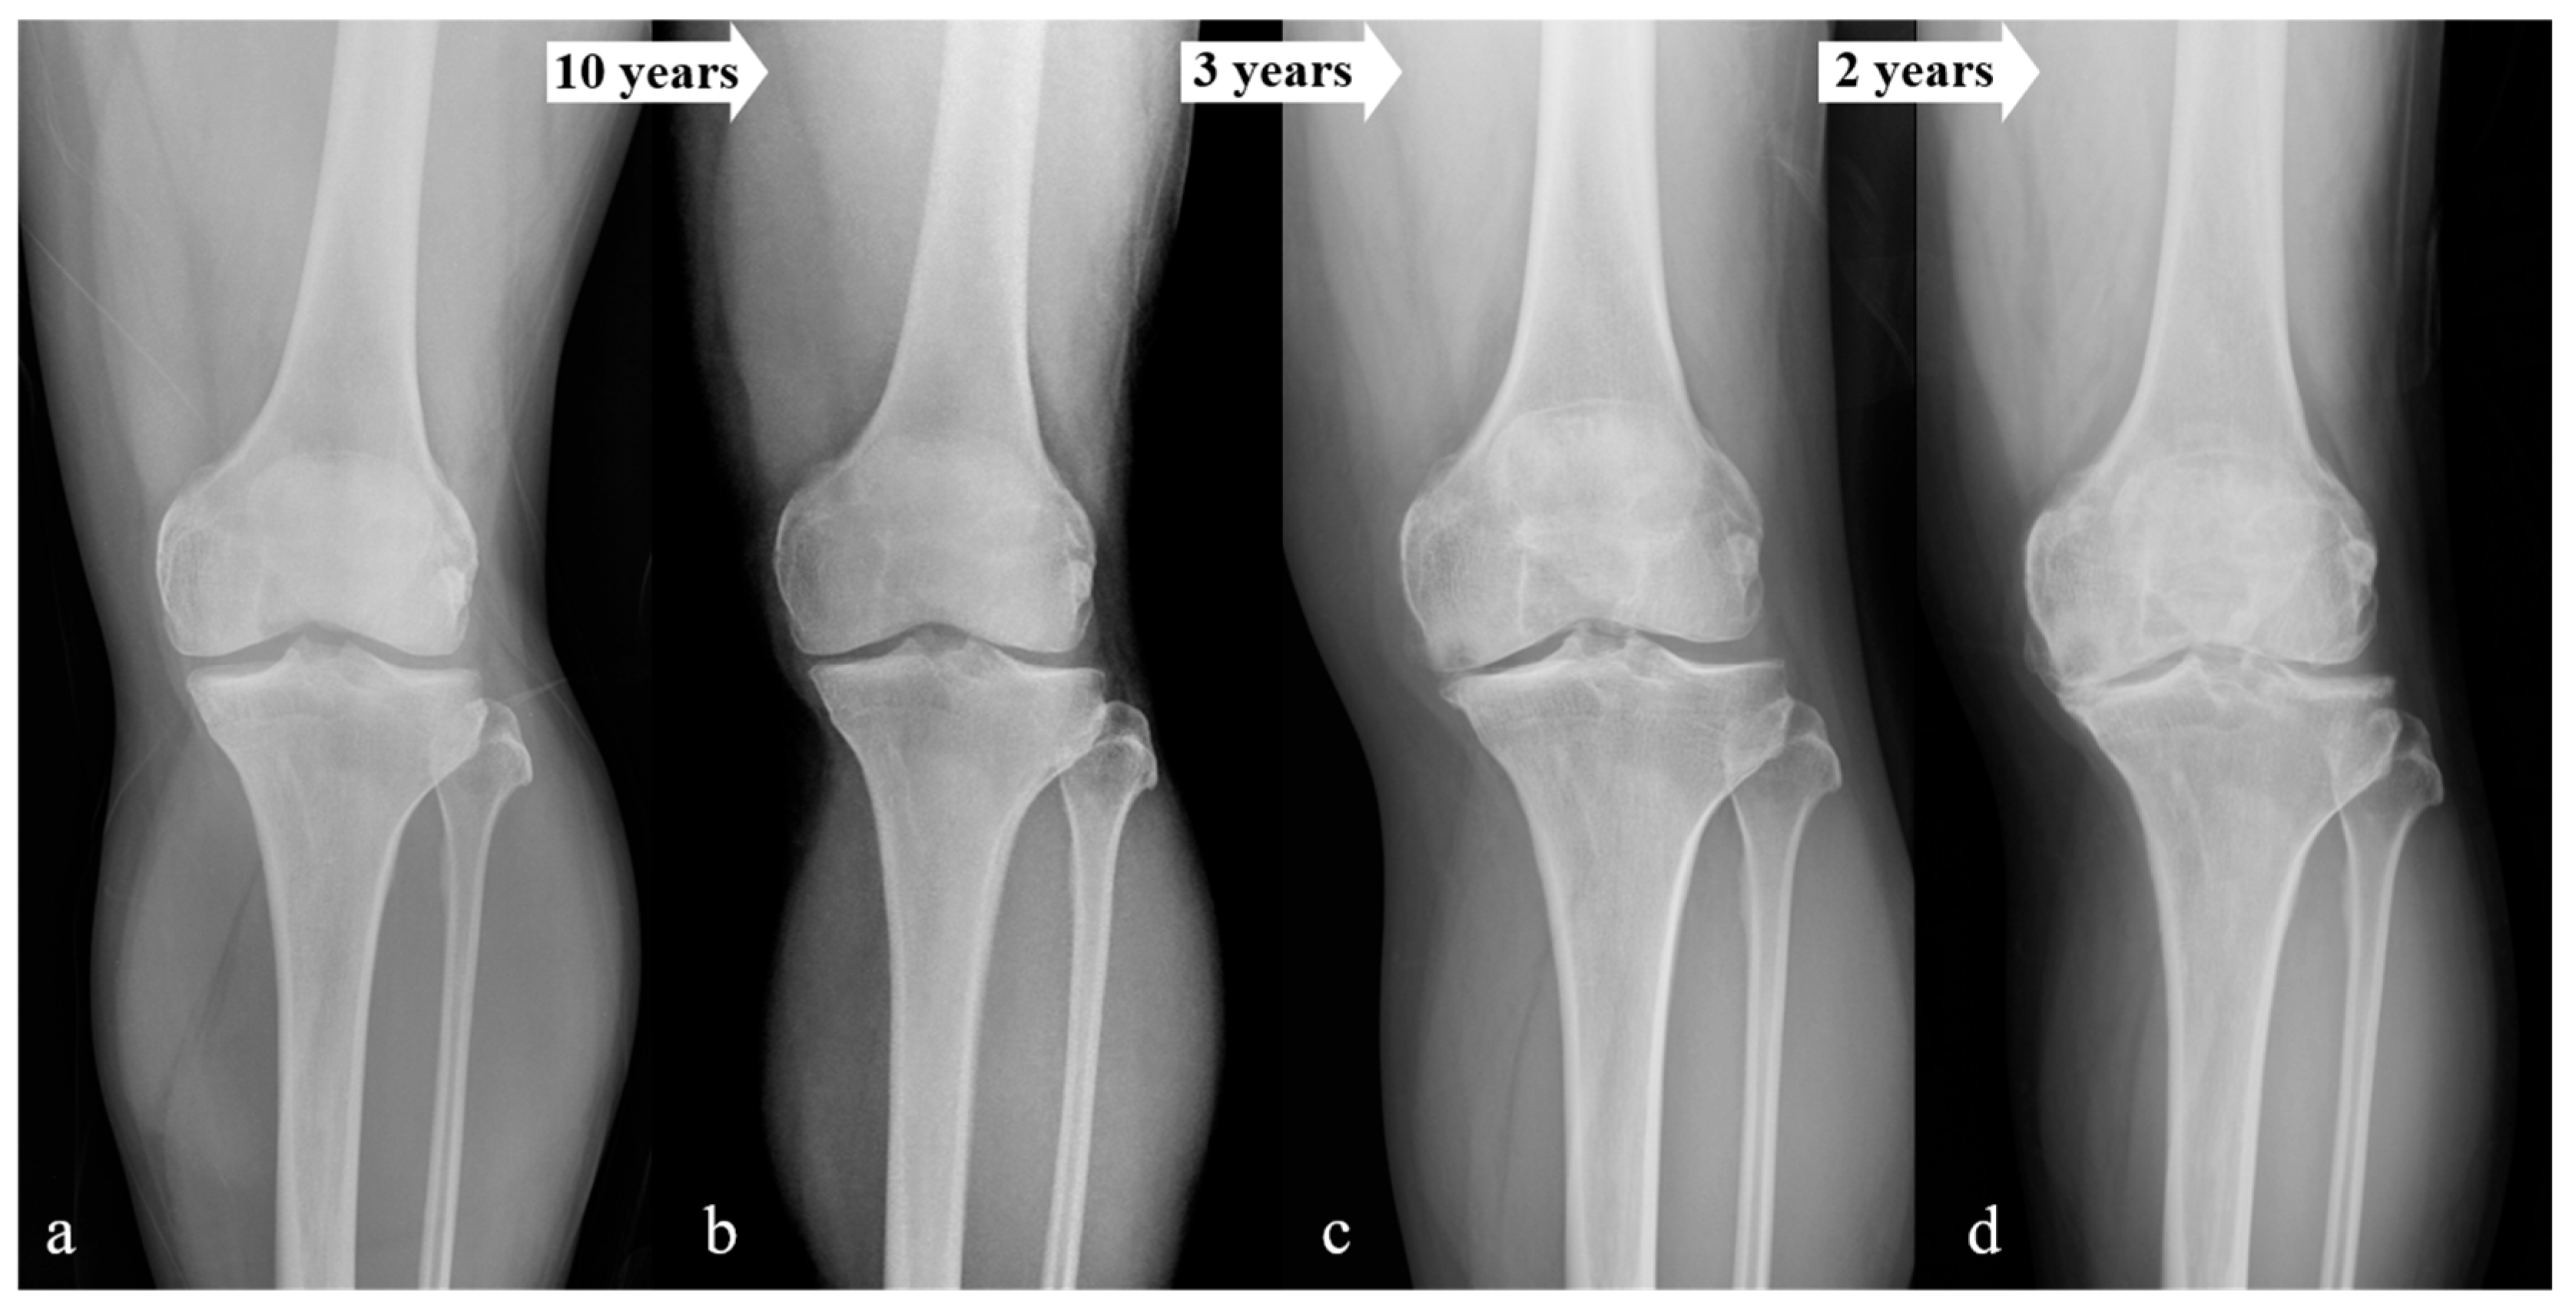

3. Results